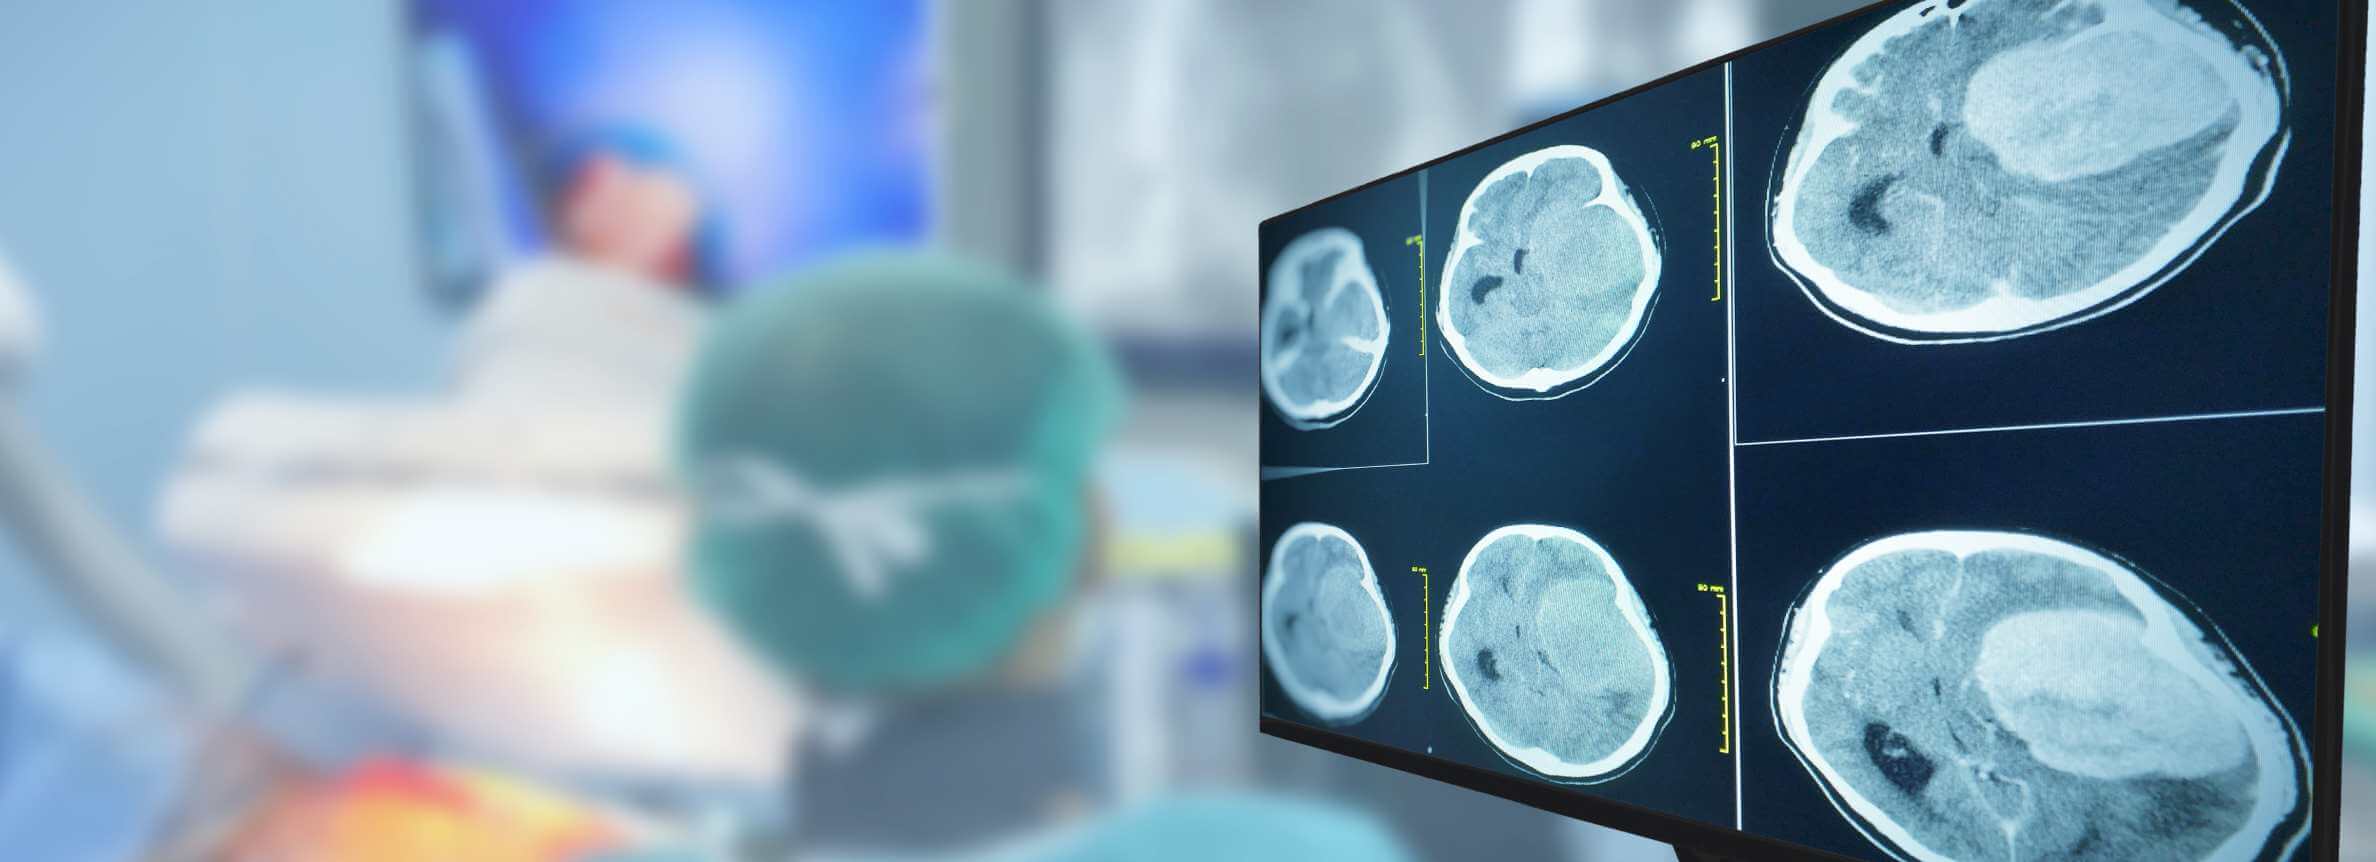

Prof. Gansauge's clinical experience in treatment with dendritic cells in Germany demonstrates its effectiveness with measurable results. His approach uses fresh, unfrozen dendritic cell vaccines. This maintains optimal cellular function and allows for targeting actual tumor antigens – distinguishing his method from clinics that freeze and store cells. Patients can see clear outcomes through MRI or CT scans. Scans may reveal shrinkage of glioblastoma cells, stabilization, or complete response to treatment.

During the entire course of treatment of glioblastoma, the patient remains under the supervision of a general practitioner, neurologist, and oncologist. In addition to clinical examinations, imaging diagnostics may be required – in this case, computed tomography (CT) is performed.

Clinical neurological evaluations and CNS visualization (e.g. MRI) help to do this. These require regular hospital visits. After the results assessment is made, medical team makes adjustments in the treatment, where necessary.